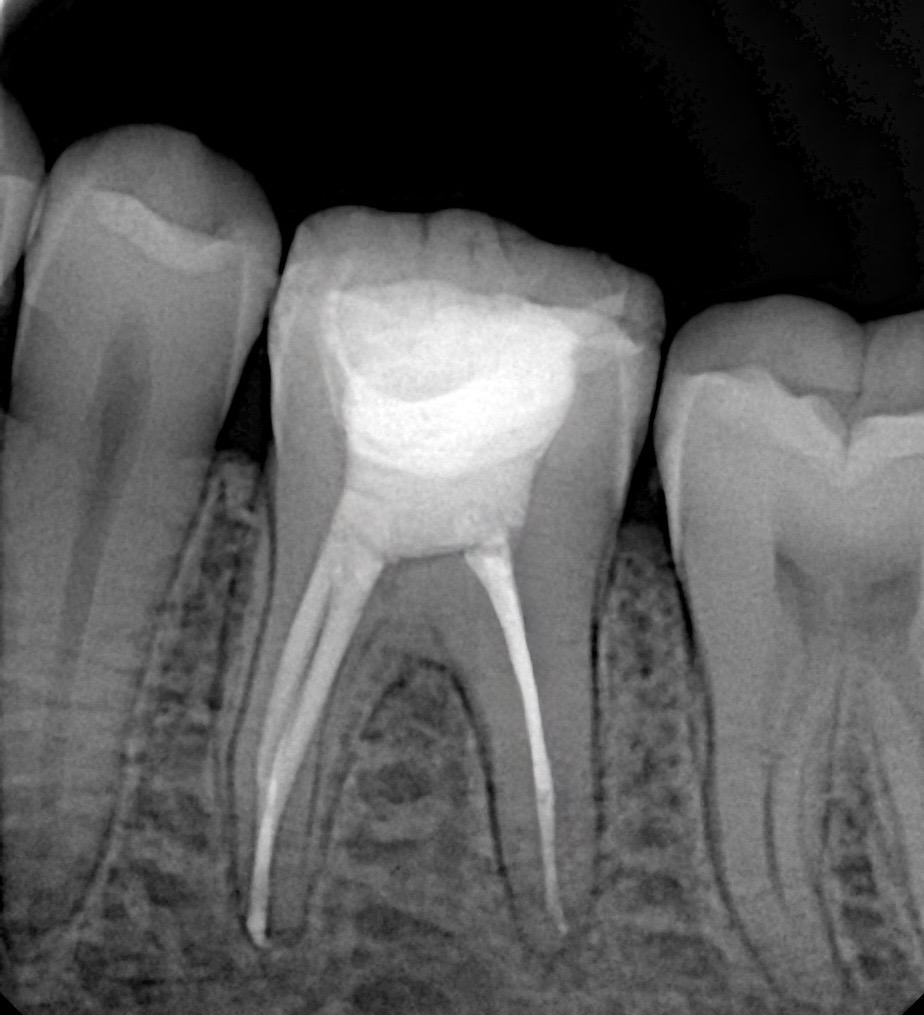

- Post-operative radiograph confirms dense 3D obturation to working length.

4. Obturation

The canals were obturated using:

- Bioceramic sealer (Calcium Silicate-based)

- Single cone hydraulic condensation technique

This ensured excellent apical sealing, bioactive dentin tubule penetration, and minimal extrusion risk.